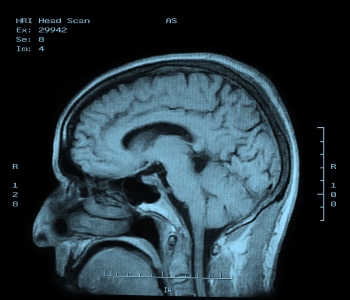

This process works by placing the body in a strong static magnetic field so that all the nuclei are oriented in the same direction. A varying field is then created to perturb the atoms locally; this re-orients them from their starting position. When that varying field is removed, the cell processes back to the static position. Different cells relax at different rates, ranging from tens of milliseconds to over one second, and the decay signals given off as the cells move back – in the 1 to 300 MHz range – create the image (see Figure 5). It is these differences in the relaxation timing that allow the system to discriminate different kinds of tissues.

Figure 5: MRI image of the brain.